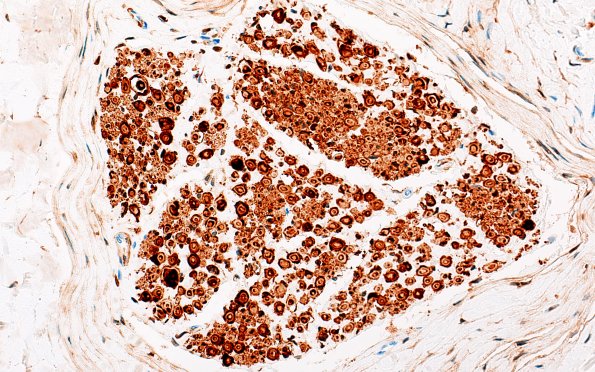

20B1 Artifact, delayed fixation (Case 20) S100 40X 1

20B1,2 S100 immunoreactivity appear to demonstrate multiple Schwann cell lamellae. (S100 IHC)